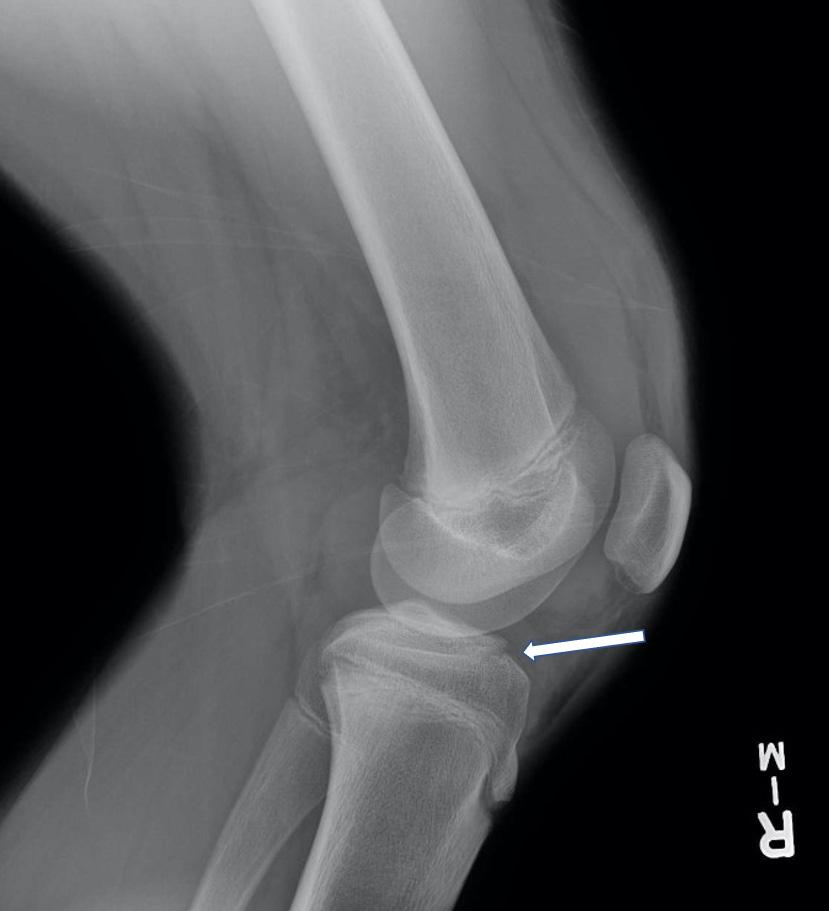

CONCLUSION

When evaluating patients in the ED, it is important to review any prior available test results for abnormalities, even if the results do not specifically correlate with the chief complaint. Our case highlights a patient who presented with finger ring entrapment and a missed diagnosis of leukemia who unfortunately succumbed to his medical illness. We hope this case presentation drives home the point for all physicians to acknowledge and act on all available results in the ED.

The authors attest that their institution requires neither Institutional Review Board approval nor patient consent for publication of this case report. Documentation on file.

Clinical Practice

Cases in Emergency Medicine 308 Volume 6, no. 4: November 2022